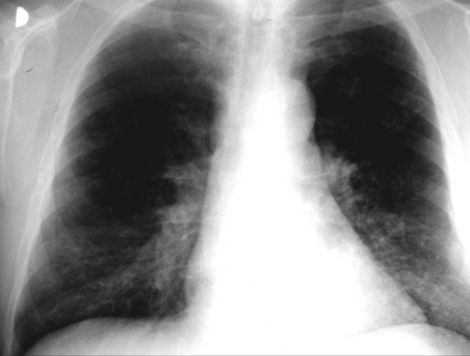

1. plucnica

1. astma